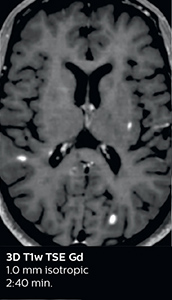

This is an example of acute ischemic stroke with distal occlusion of the right posterior cerebral artery. Note the improved visibility of the ischemic territory on the diffusion weighted image with high b-value. The 3D FLAIR shows a distal PCA occlusion. The fast SWIp depicts the thrombus on the isolated second echo image. The total scan time (including SmartBrain, preparations and a fast 3D T1w TSE Gd) is 8:00 minutes.